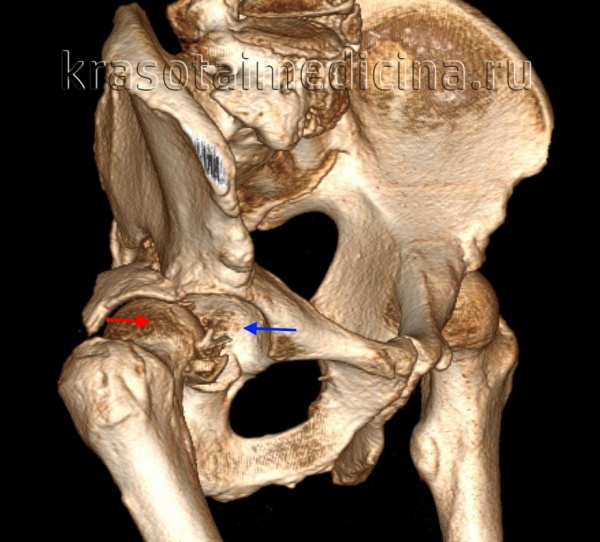

КТ таза. 3D-реконструкция. Красная стрелка – вывихнутая головка бедренной кости, синяя стрелка – «пустая» вертлужная впадина.